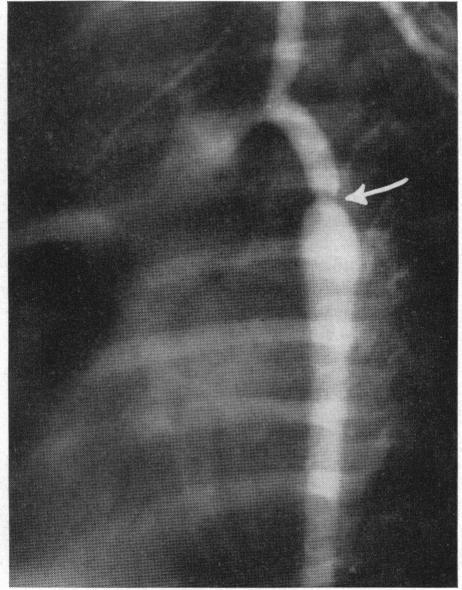

Patent ductus arteriosus and coarctation of the aorta are among the commonest causes of congestive heart failure early in life. When medical therapy fails to control heart failure in these cases, surgical division of the ductus or excision of the coarcted segment can be performed. But the recognition of these anomalies in infancy is more difficult than in childhood or adult life. Retrograde thoracic aortography is a technique which permits positive identification. In the presence of patent ductus arteriosus, opacification of the pulmonary arteries from the descending aorta will be clearly shown; if coarctation is present, its position, severity, and the length of the involved segment can usually be demonstrated. Properly employed, retrograde brachial aortography is a relatively safe and effective diagnostic procedure.

动脉导管未闭和主动脉缩窄是生命早期充血性心力衰竭最常见的病因。当药物治疗无法控制这些病例的心力衰竭时,可进行动脉导管的手术分离或缩窄段的切除。但在婴儿期识别这些异常比在儿童期或成年期更困难。逆行胸主动脉造影是一种能够进行明确诊断的技术。在存在动脉导管未闭的情况下,降主动脉向肺动脉的造影剂充盈将清晰显示;如果存在主动脉缩窄,其位置、严重程度以及受累节段的长度通常可以显示出来。正确应用时,逆行肱动脉主动脉造影是一种相对安全有效的诊断方法。